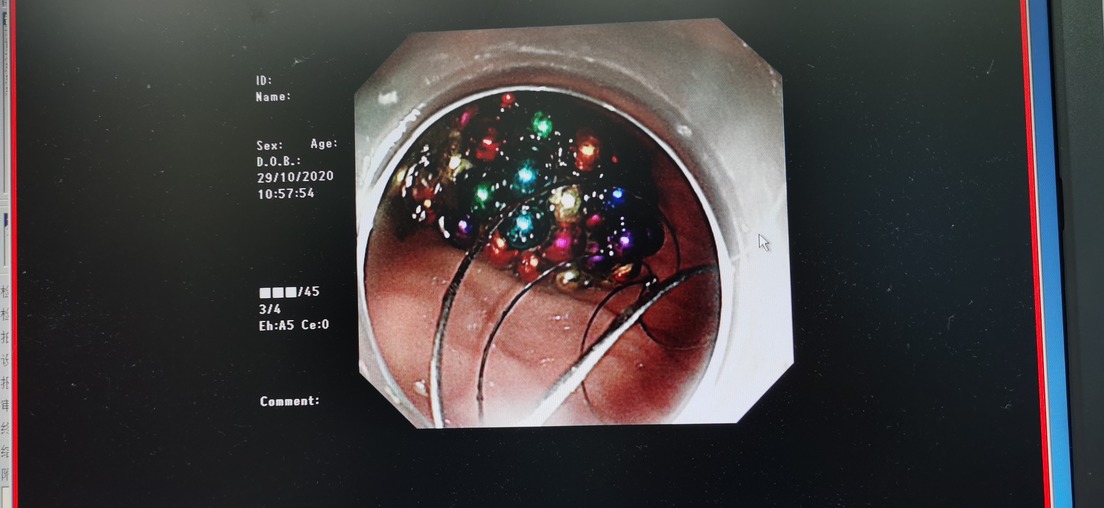

Según informa el hospital, tras más de cuatro horas de cirugía, en las que fue utilizado equipo especializado de gastroscopía, los médicos pudieron recuperar del estómago del menor las 123 cuentas de 0,5 centímetros que había ingerido.